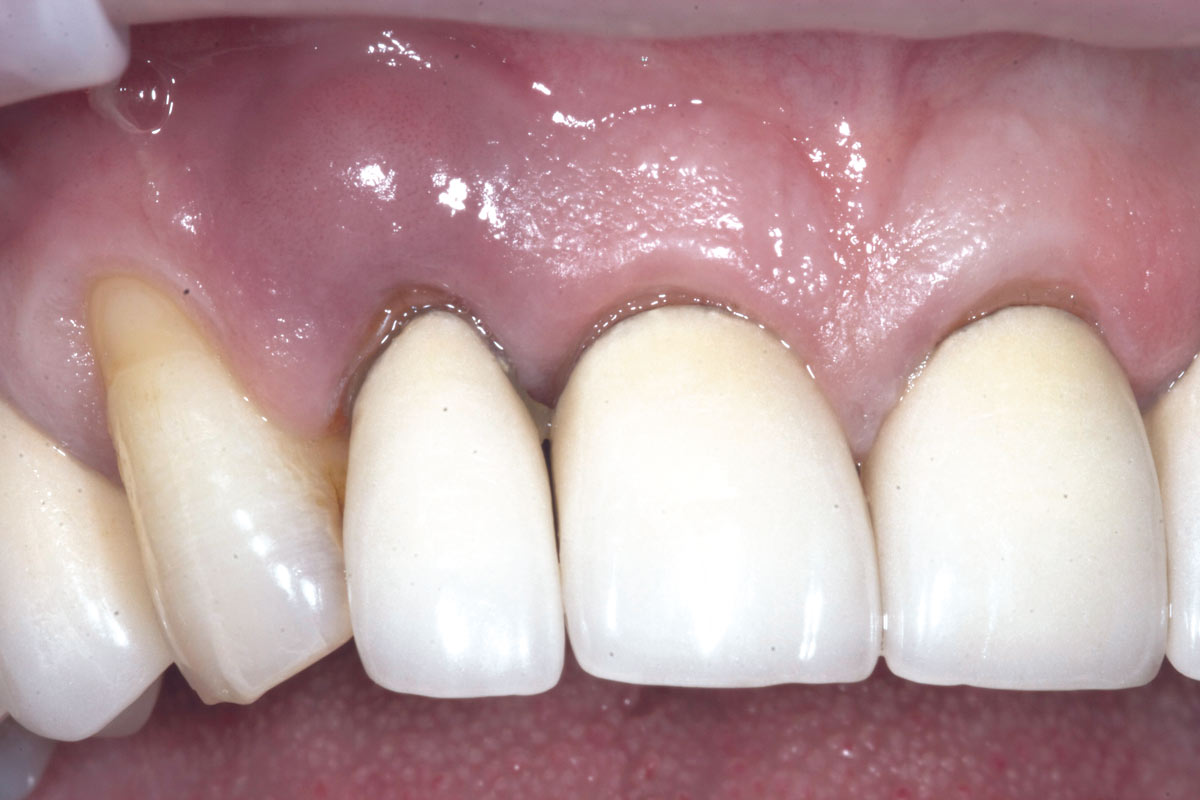

1/19 - Initial situation: Inflammated tooth #12Bone augementation with maxresorb® - Dr. R. Cutts

Initial situation: Inflammated tooth #12